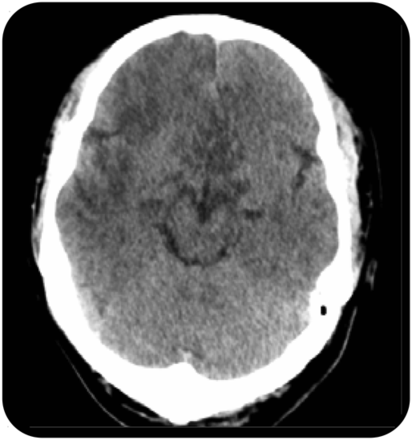

脑CT显示大规模非对称hypodensities在两个半球,主要位于额叶,顶叶和颞叶(图1)。蛛网膜下腔出血后排除腰椎穿刺显示清楚CSF与高程的蛋白质水平(1.06 g / L)。开启压力、白细胞和血糖水平在正常范围内。未发现红细胞,没有生物样本中发现了文化。考虑到既存上质量和第二和第三颅神经的损伤,垂体卒中,特点是霹雳头痛,视觉恶化,眼肌麻痹,脑膜刺激的迹象,意识改变,和激素功能障碍,成为另一个重要的考虑因素。然而,单边巴宾斯基签署和脑CT清楚地表明,病变不仅局限于脑下垂体及其邻近结构。